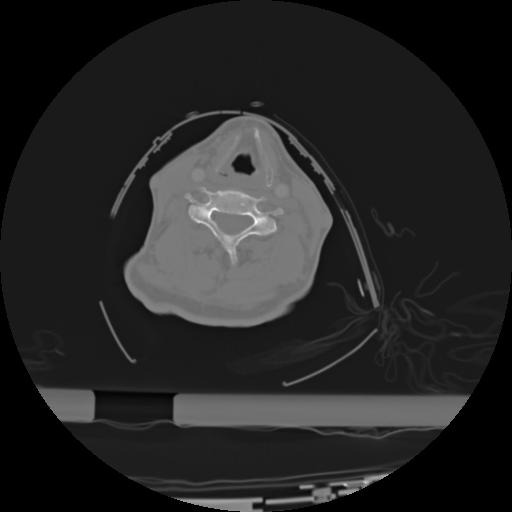

21 ANGIO,CE,Axial,3.0,ANGIO,,